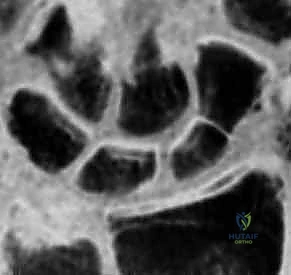

* التصوير بالرنين المغناطيسي (MRI): هو المعيار الذهبي لاكتشاف الكسور المخفية وتقييم التروية الدموية للقطب القريب.

* الأشعة المقطعية (CT Scan): تستخدم لتحديد شكل الكسر بدقة ثلاثية الأبعاد والتخطيط للعملية الجراحية.